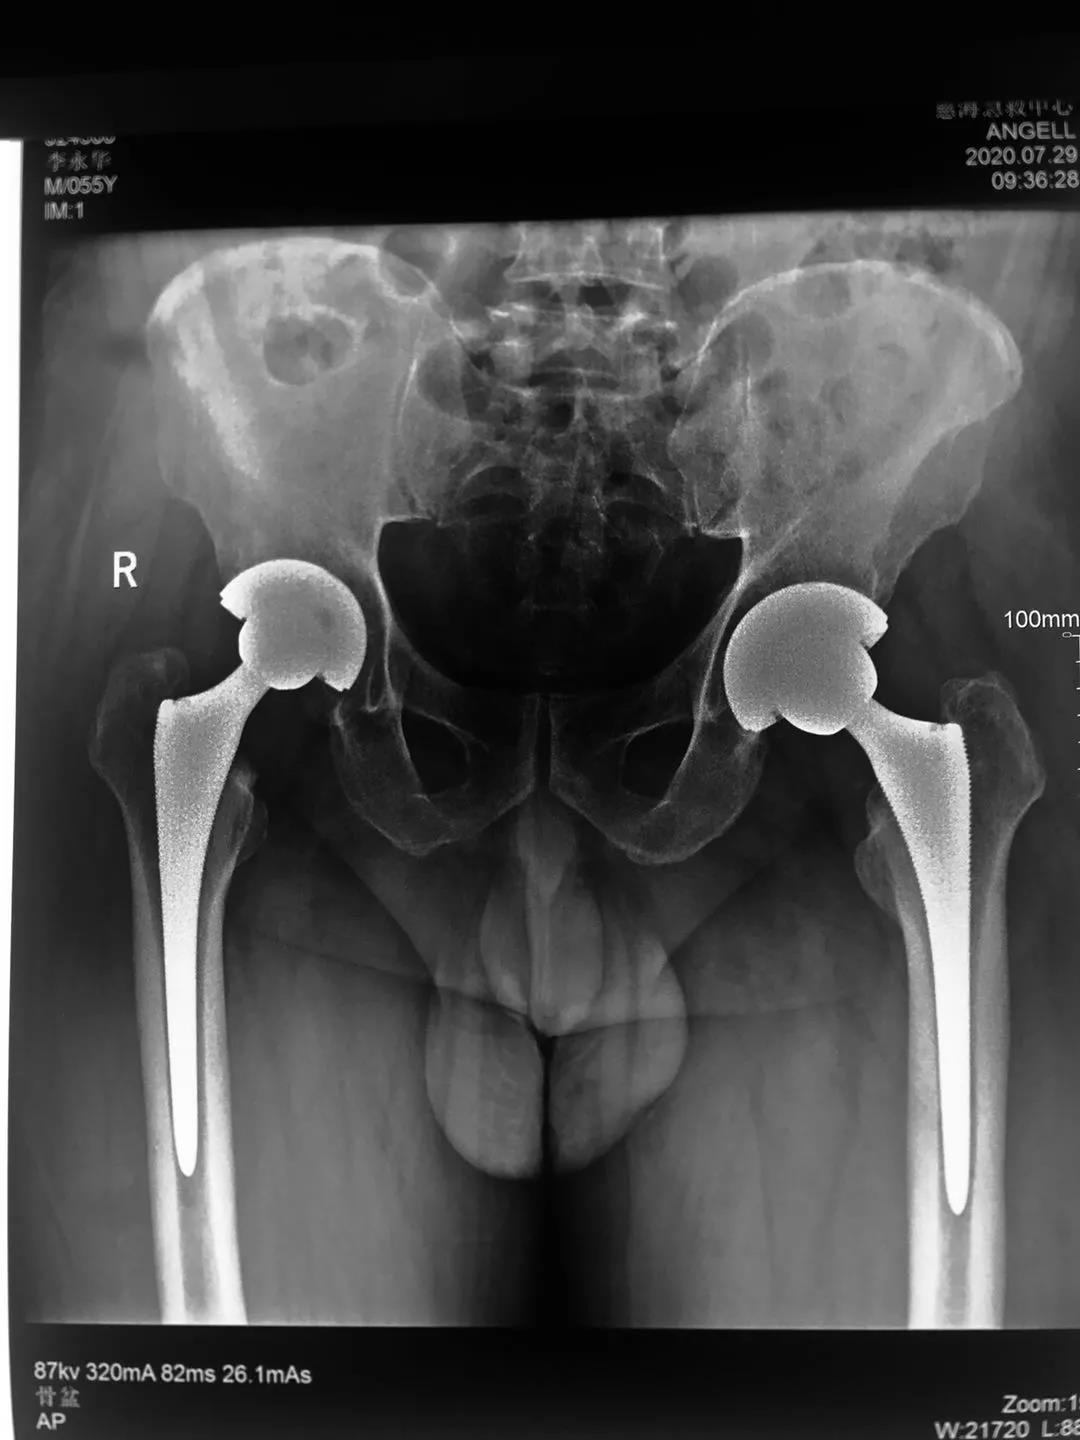

患者一年前雙側(cè)髖疼痛,到骨科就診,確診為股骨頭壞死,由于左髖關(guān)節(jié)痛疼較重給予行左髖關(guān)節(jié)置換,術(shù)后恢復(fù)良好。今年右髖關(guān)節(jié)痛疼加重再次住院,入院后完善相關(guān)檢查,根據(jù)患者病情,征得患者及家屬同意,順利施行了右髖關(guān)節(jié)置換術(shù),術(shù)前片子提示患者骨盆傾斜較重,術(shù)前評(píng)估設(shè)計(jì)術(shù)中假體植入角度,術(shù)后完美恢復(fù)雙下肢長(zhǎng)度與雙側(cè)髖關(guān)節(jié)旋轉(zhuǎn)中心,患者非常滿(mǎn)意,目前患者情況良好,已出院。

術(shù)后復(fù)查拍片